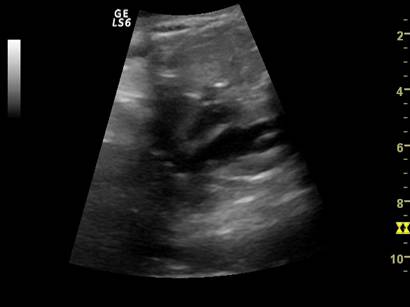

Fig. nr. 268. Formatiune anecogena abdominala fetala independenta de rinichi, la 28 sapt,ulterior in crestere la copilul de 3 ani

Fig. nr. 269. La peste 3 ani de la diagnosticul intrauterin, formatiunea tumorala abdominala ajunge la dimensiunea de 12 cm diametru si cu o structura inomogena cu mici hiperecogenitati sugestive ptr un teratom